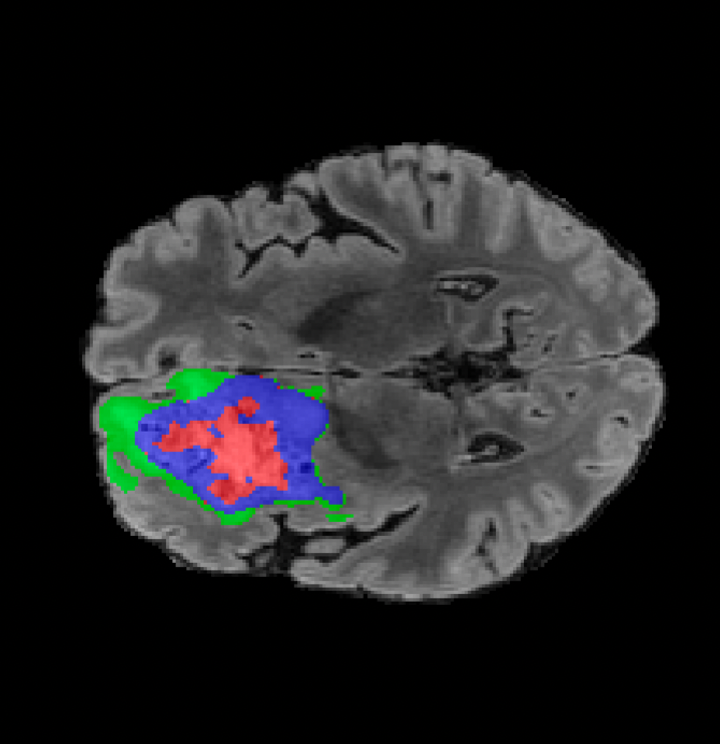

Tumour Information Preservation. For the brain tumor segmentation, we use a Swin UNETR model[27, 70], trained with random rotation, and intensity as data augmentation. In Figure 5, we highlight the tumor profiles of the generated MRIs compared to the ground truth tumour profile. In the test set with human ground-truth annotations (), the real MRI Dice score is 85.15 while the generated MRIs from a single slice have a dice score of 83.09. This shows how the generated MRIs indeed preserve the tumor information and can act as an affordable and informative pseudo-MRI, before conducting an actual costly MRI examination in hospitals.

On the test set with human ground-truth annotations (), the brain volumes generated from single slice input preserve the volume of the different tumour components (paired t-test, for all 3 classes) (see Table 3). The real MRI Dice scores are put for reference to our generated MRIs. X-Diffusion outperforms baselines TPDM [36] and ScoreMRI [18] in tumour preservation (see Table 3 and Figure 12). We ran experiments comparing the tumour segmentation Dice Score varying X-Diffusion configurations. The multi-slice input X-Diffusion achieves a marginally better Dice Score than the single-slice input model (83.47 83.09). We also ran experiments with slice input used for volume reconstruction intersecting or not with tumour. We observe on average a drop of 6% Dice Score (see Table 3). Further away from the tumour the input slice for volume reconstruction is selected, and we observe a linear decrease in tumour segmentation Dice Score with the lowest value of 77.21 Dice Score (see Figure 15).

This shows how the generated MRIs indeed preserve the tumour information and can act as an affordable and informative pseudo-MRI, before conducting an actual costly MRI examination in hospitals. Given that our model has been trained on brain scans all with tumours, we expect to see hallucinations of tumours in healthy scans. We report two cases of failure of our model in Figure 16. Hallucinations of tumours on healthy samples represent 2% of the test set.